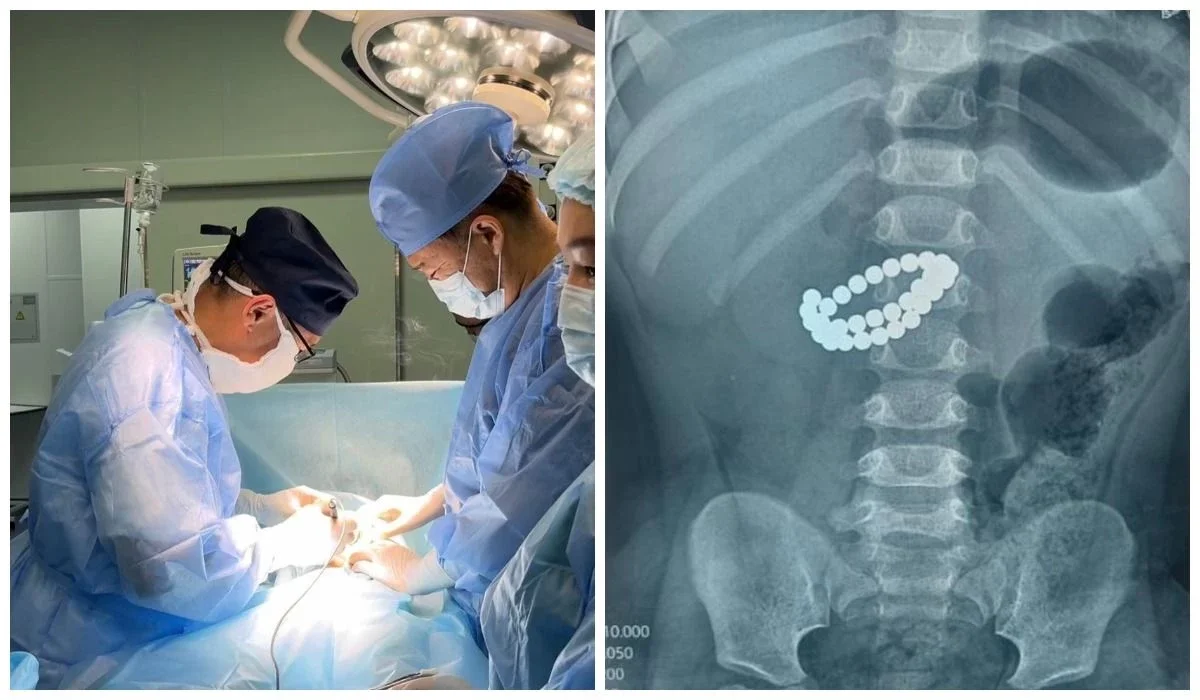

Алматы әкімдігінің мәліметінше, бала 31 магнит жұтып қойып, ішегіне ауыр зақым келіп, перитонит белгілерімен өте ауыр жағдайда жеткізілген.

Хирургтер магниттерді алып, жіңішке ішектегі зақымдарды қалпына келтіріп, құрсақ қуысын толық тазарту шараларын жүргізген. Дәрігерлердің айтуынша, бұл ота баланың өмірін сақтап қалудың жалғыз жолы болған.